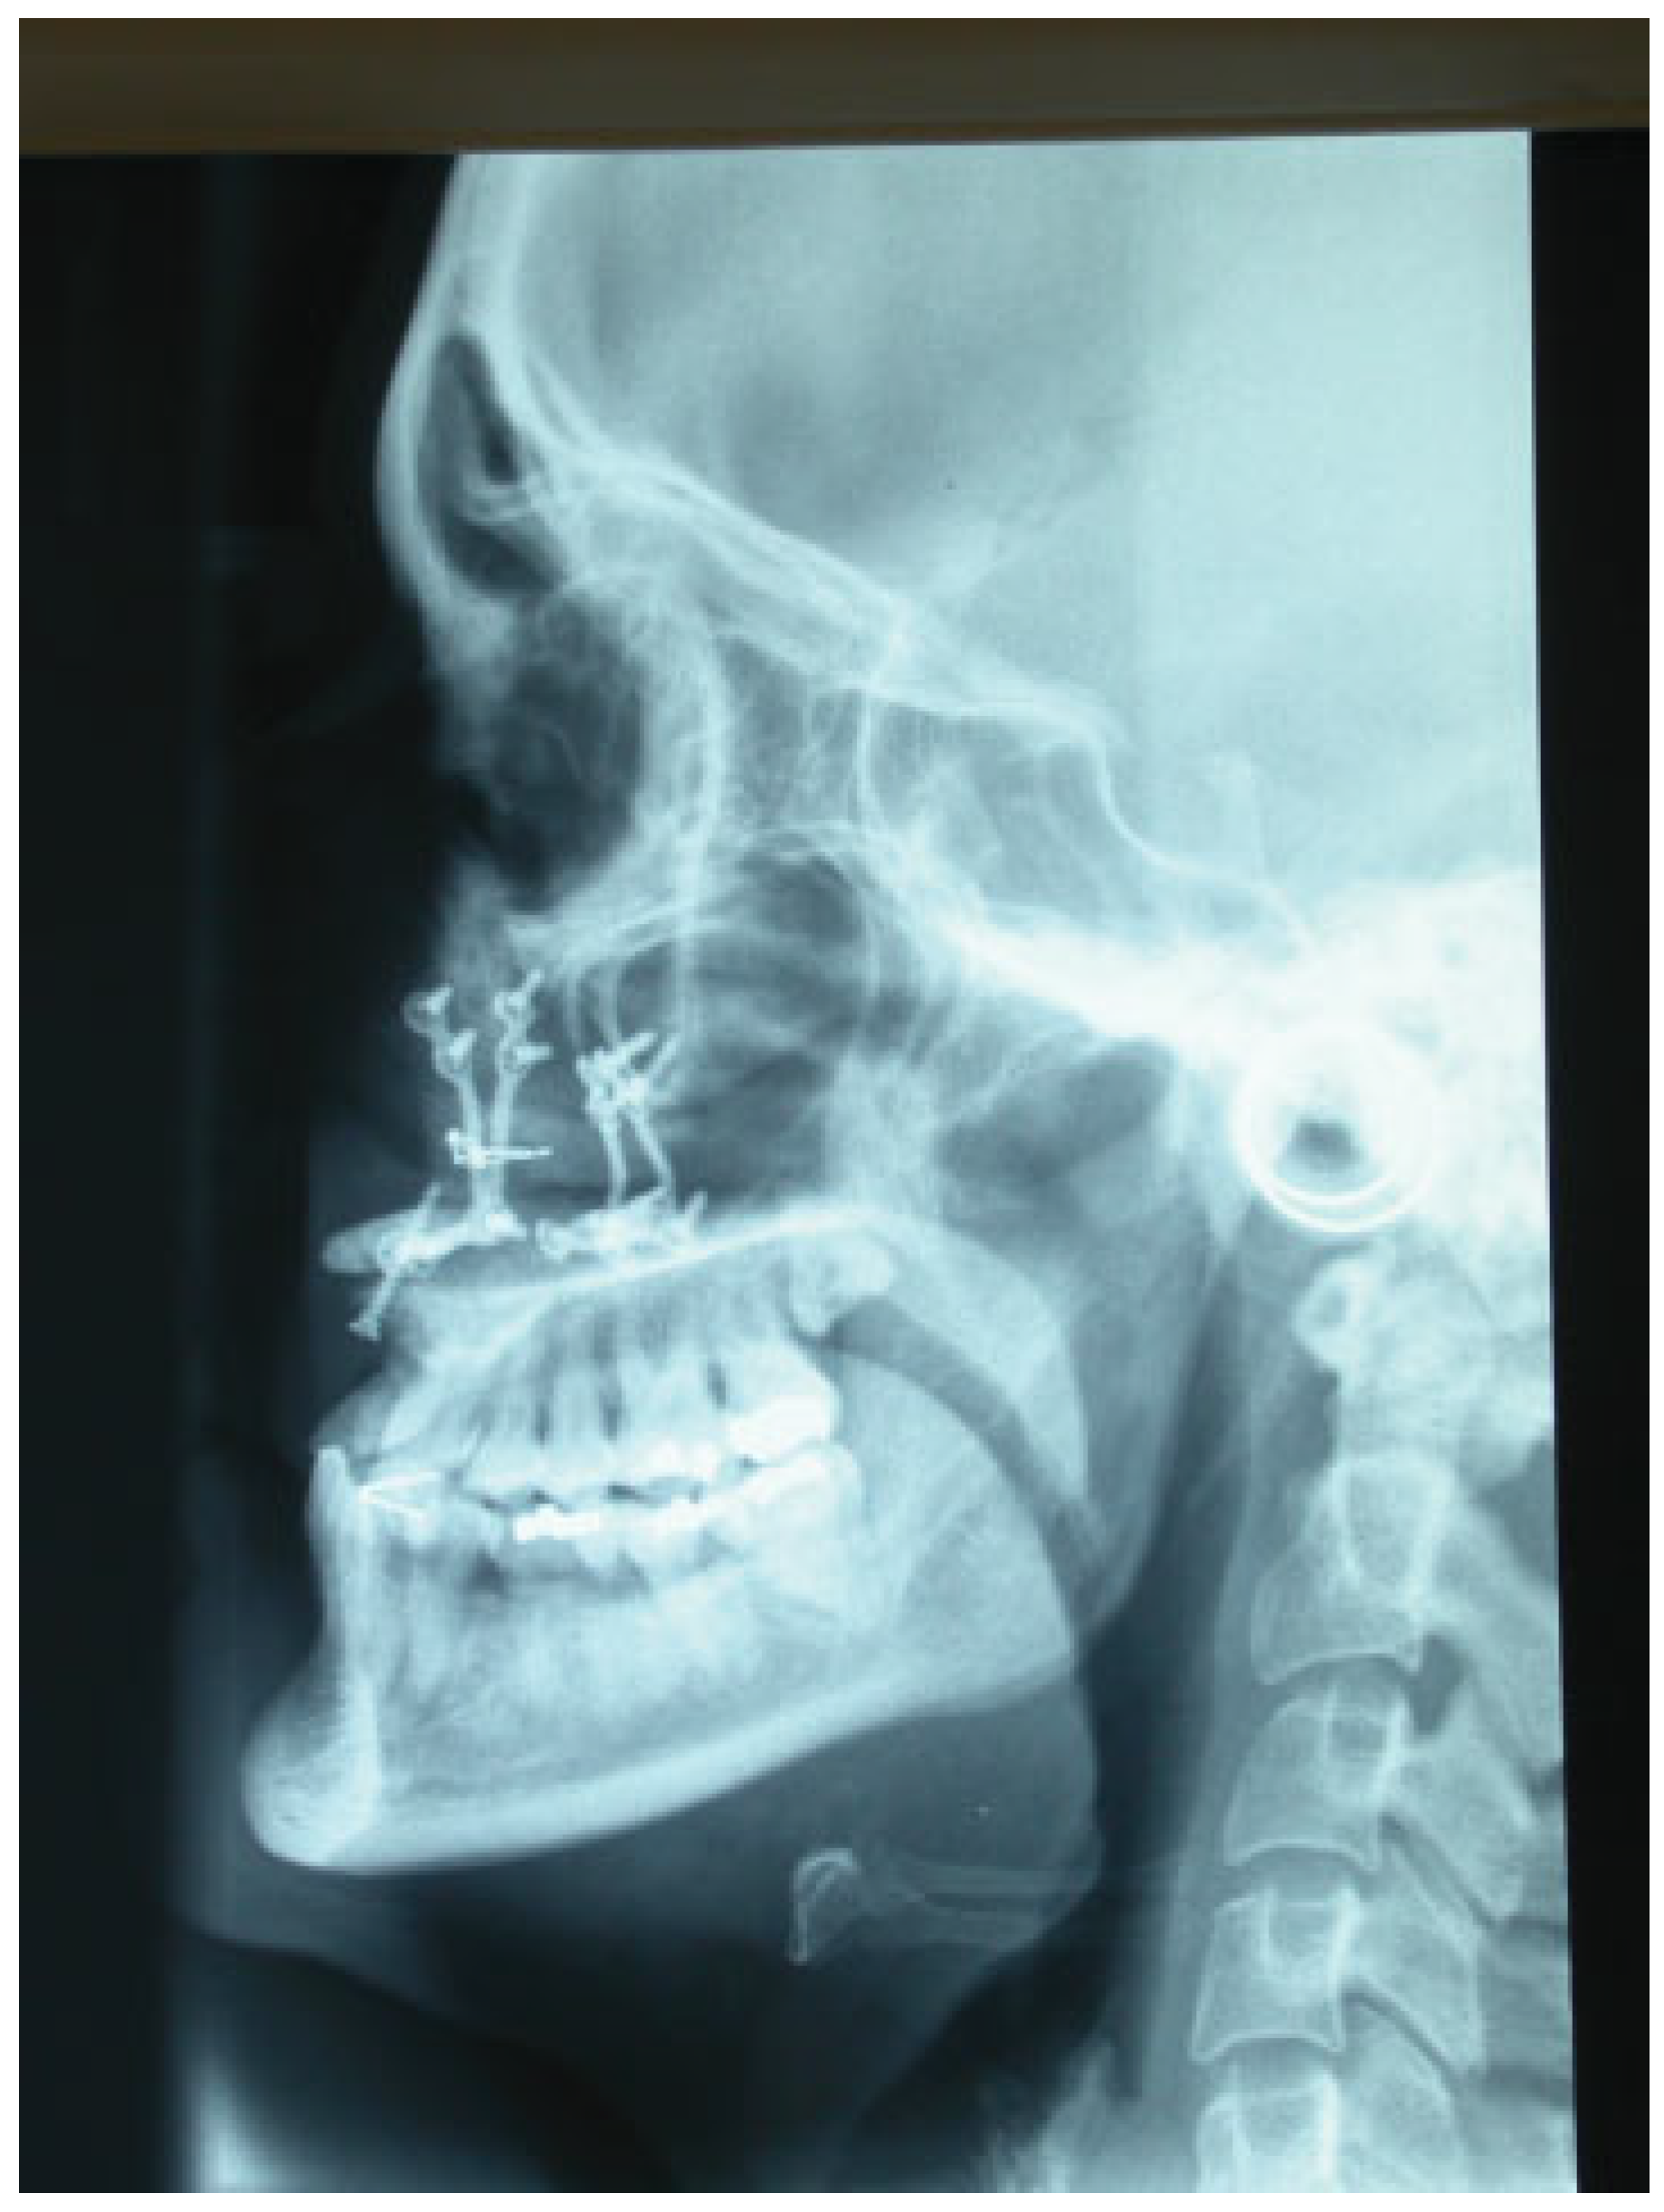

Figure 6.

Tele-lateral radiograph. The grafts are fixed with stainless steel wires and the maxillary fixation is performed with titanium miniplates.